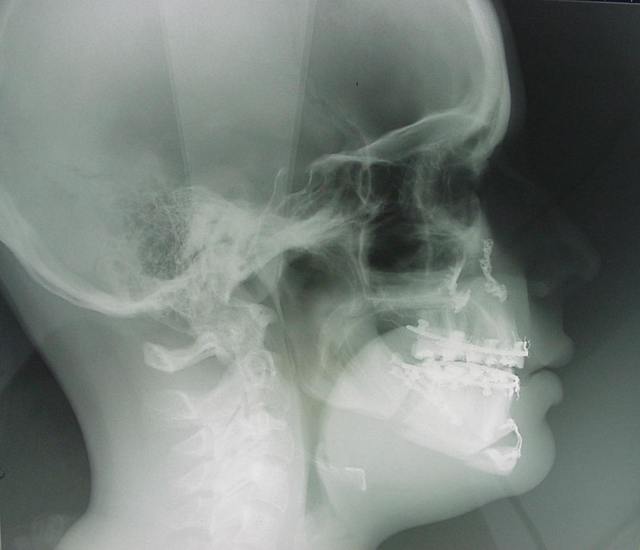

chir d'avancée mand et max

voici les radios de ma chir, j'aurais les photos lundi pour ceux que ça intéresse.